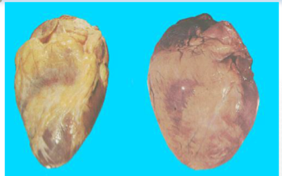

(1)心脏:心脏的病变主要为左心室肥大。由于外周阻力增加,血压持续升高,左心室因压力性负荷增加发生代偿性肥大。心脏肥大,重量增加,可达400g(正常约250g~350g)以上。左心室壁增厚,可达1.5~2.5cm(正常为<1.2 cm),乳头肌和肉柱增粗变圆,但心腔不扩张,甚至略缩小,称为向心性肥大(concentric hypertrophy)。光镜下:心肌细胞变粗、变长,核大而深染。病变继续发展,肥大的心肌细胞与间质毛细血管供血不相适应,肥大心肌细胞逐渐出现供血不足,心肌收缩力减弱,左心室失代偿,心腔扩张,称为离心性肥大(eccentric hypertrophy),如果合并AS,可进一步加重心肌供血不足,促进心力衰竭。

由高血压引起的心脏病称为高血压性心脏病(hypertensive heart disease)。病人血压常在180mmHg(24kPa)/120mmHg(16kPa)以上。临床上表现为左心界扩大及反复发作的左心衰竭。心电图示左室肥大及劳损。

正常 高血压心脏 |